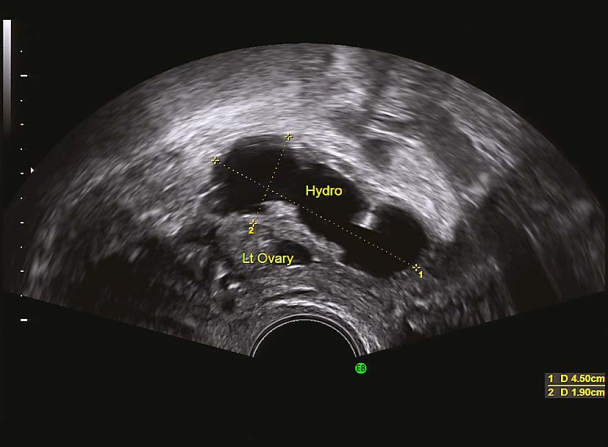

卵泡生长发育监测(排卵前期) 输卵管积水超声表现 输卵管积水超声表现

(2)激素测定:排卵障碍和年龄≥35岁女性均应行基础内分泌测定,于月经周期第2~4日测定FSH、LH、E2、T、PL基础水平。排卵期LH测定有助于预测排卵时间,黄体期P测定有助于提示有无排卵、评估黄体功能。